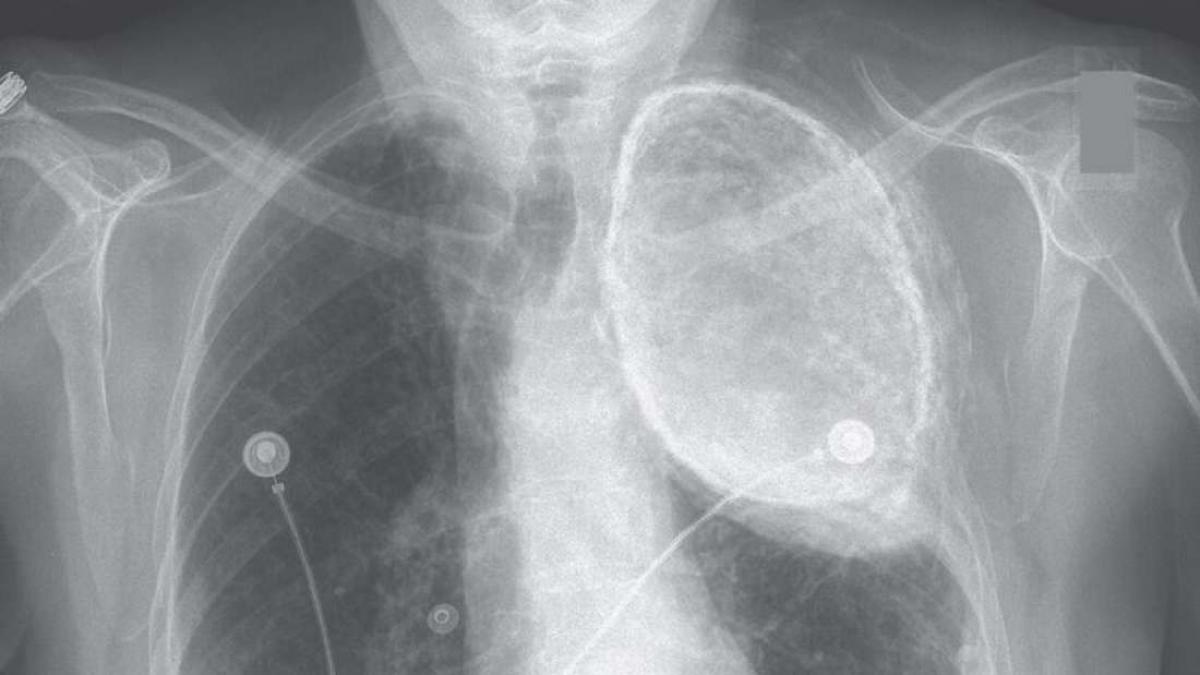

Insa de vreo 4 zile nu vrea sa dispara acest disconfort ba chiar sa extins in spate. Dureri in piept si dureri ale bratelor umerilor si maxilarului. De un am incoace am dureri in piept de fapt nu sunt dureri ci arsuri cu amorteala si apasare. Raguseala dureri de gât.

Durerea in piept intr un atac de cord la femei poate fi doar exprimata ca un disconfort la nivelul gatului maxilarului umerilor si sau spatelui. Aceasta se produce atunci când acidul gastric care se află în mod normal în stomac pătrunde prin sfincterul gastro esofagian mușchi care acționează ca o valvă ce se contractă în timpul digestiei în esofag unde poate irita mucoasa cauzând durere care poate dura de la câteva minute la câteva ore. Regurgitatie întoarcerea mâncarii sau reflux de lichid acru reflux acid senzatie de nod în gât. Dificultate la înghitire disfagie tuse seaca.